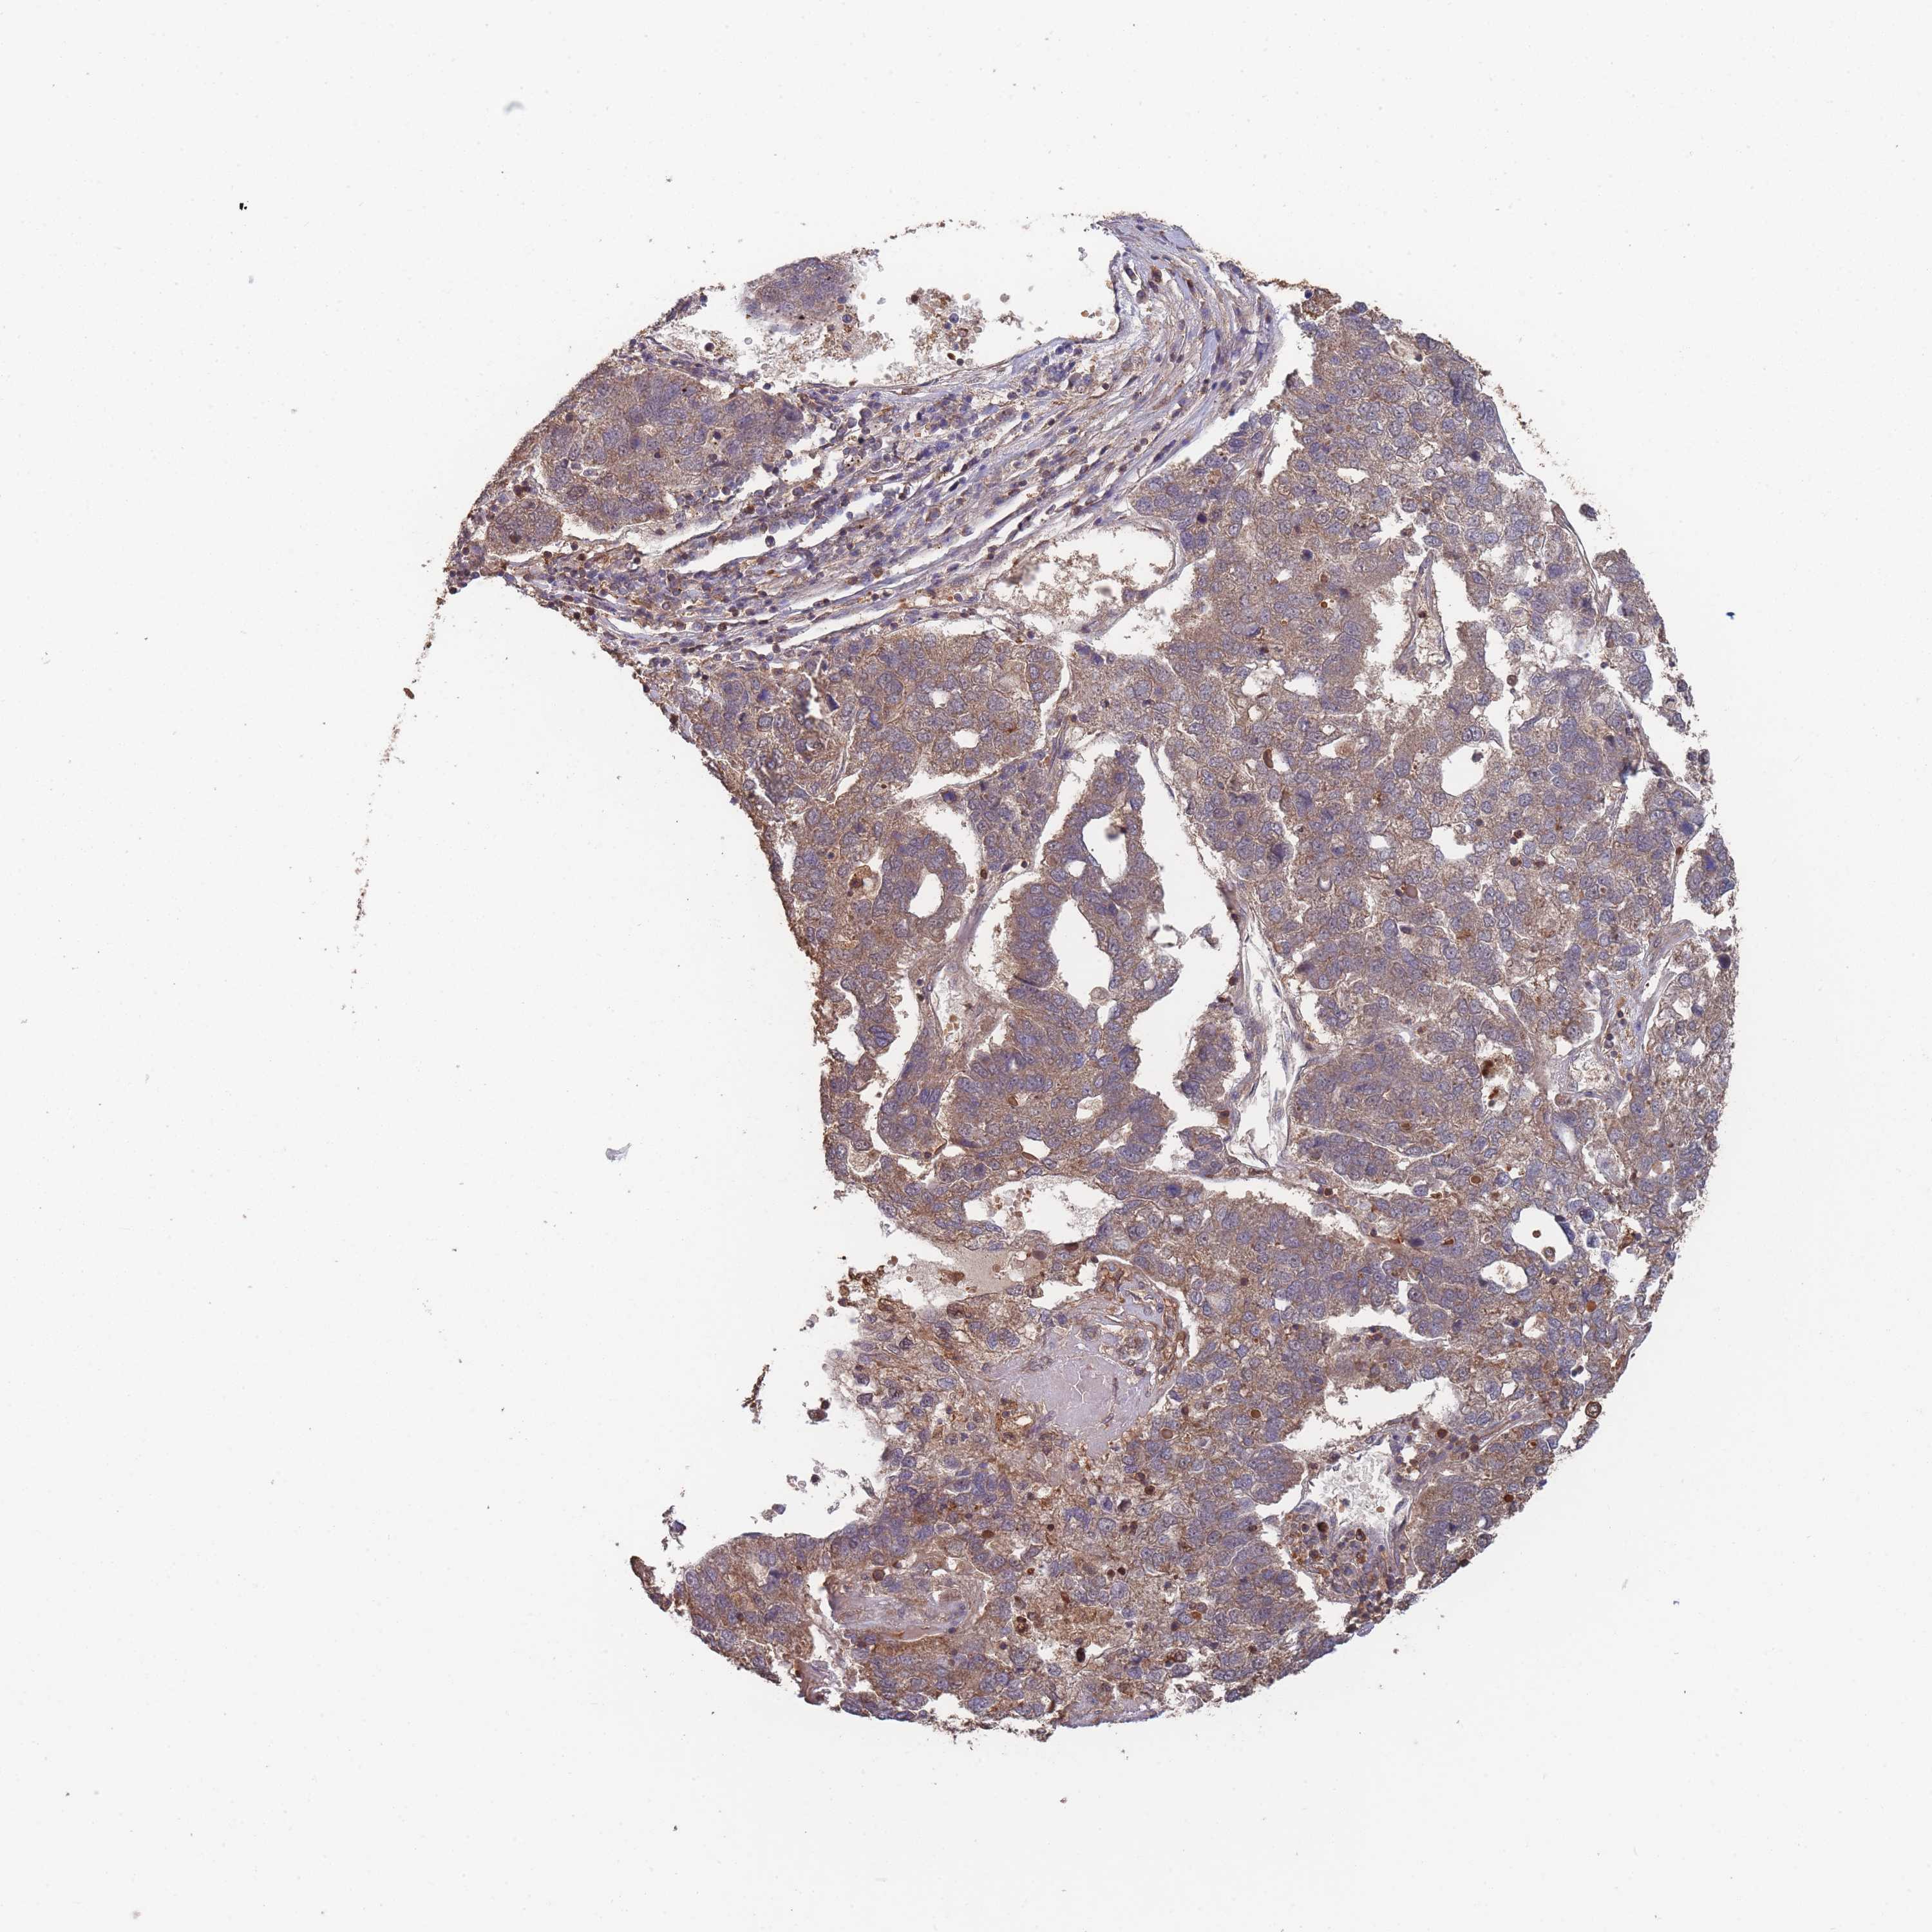

PANCREATIC CANCER - Protein expressioni

A mouse-over function shows sample information and annotation data. Click on an image to view it in a full screen mode. Samples can be filtered based on level of antibody staining by selecting one or several of the following categories: high, medium, low and not detected. The assay and annotation is described here.

Note that samples used for immunohistochemistry by the Human Protein Atlas do not correspond to samples in the TCGA dataset.

Antibody stainingi

Antibody staining in the annotated cell types in the current human tissue is reported as not detected, low, medium, or high, based on conventional immunohistochemistry profiling in selected tissues. This score is based on the combination of the staining intensity and fraction of stained cells.

Each image is clickable and will lead to virtual microscopy that enables deeper exploration of all samples and also displays staining intensity scores, fraction scores and subcellular localization as well as patient and tissue information for each sample.

Antibody HPA050275

Staining

High

Medium

Low

Not detected

Intensity

Strong

Moderate

Weak

Negative

Quantity

>75%

75%-25%

<25%

None

Location

Nuclear

Cytoplasmic/membranous

Cytoplasmic/membranous,nuclear

Adenocarcinoma, NOS